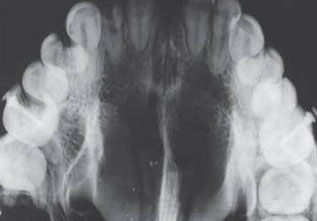

OCCLUSAL VIEW

Occlusal X-rays show the roof or floor of the mouth and are used to find extra teeth, teeth that have not yet erupted through the gums, jaw fractures, a cleft palate, cysts, abscesses or growths. Occlusal X-rays may also be used to find the position of any foreign object accidently entrapped into upper & lower jaws.